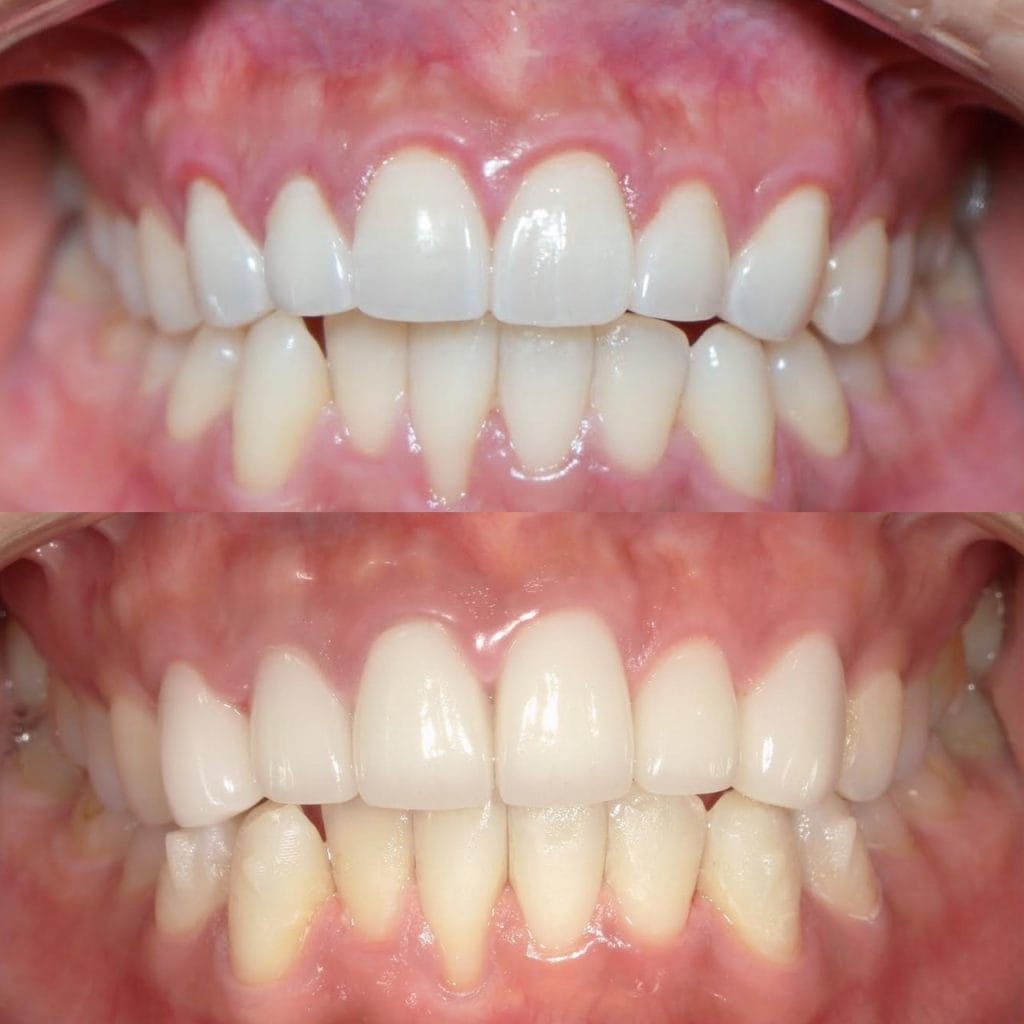

前歯が虫歯なのと、保険のプラスチックで大きく治療されていて色が悪いこと、歯並びが出っ歯気味であることを気にしてセラミックにしたいという主訴で来院された患者様です。

虫歯が大きかったところは神経治療をきちんと行い、

初診時を含めてトータル4回のご来院で完了です。

今回は前歯を下げる、歯列を整える、白すぎず自然に綺麗に見える色というご希望に沿って治療しました。